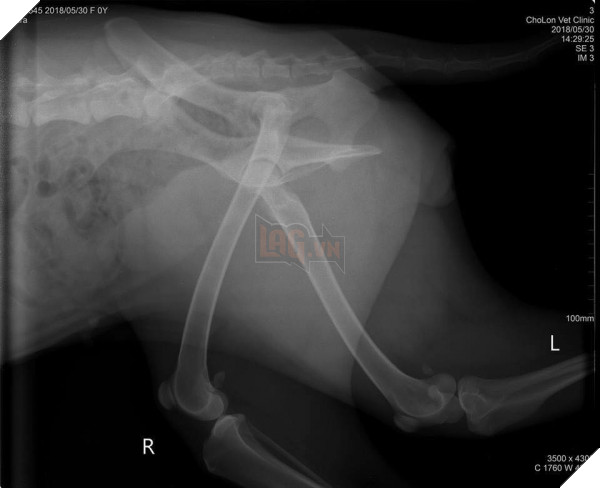

Về phía con Sen tội nghiệp, sau giây phút bàng hoàng, vội vã sờ nắn rồi tức tốc đưa đi bệnh viện, chụp chiếu mất 700.000 ngàn, và may thay  “nó chẳng sao cả, xương không gãy cái nào, chỉ bị sung huyết thùy đỉnh phổi và có dịch”. Thật là một cái kết quá có hậu cho “thanh niên ngáo” tìm đến cách nhảy lầu để trốn đi chơi.